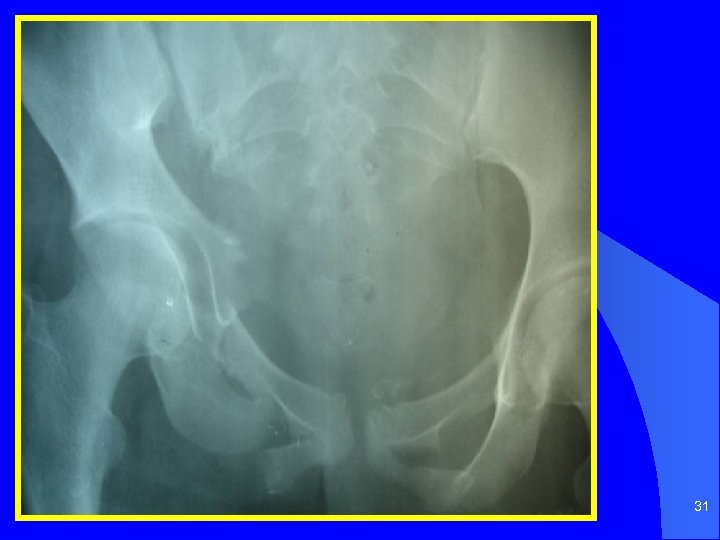

31